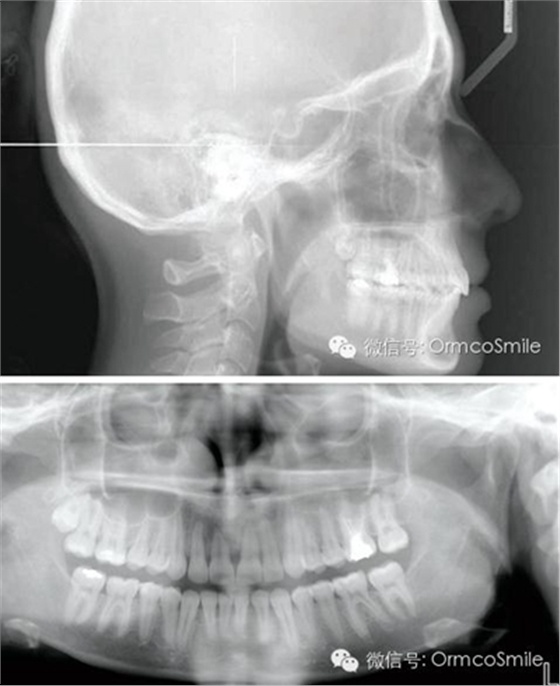

治療目標(biāo)為:遠(yuǎn)中移動上頜右側(cè)磨牙,達(dá)到安氏Ⅰ類尖牙、磨牙關(guān)系。治療前,拔除上頜左側(cè)第三磨牙,將一直徑2mm,長14mm的鈦骨釘植入上頜腭中縫,位于切牙孔后4-5mm,中線旁3-4mm。用1.3mm直徑的鉆助攻植入螺紋釘。一周之后,取印模并灌制模型,將螺紋釘?shù)念^部用蠟包圍,從螺紋釘上延伸出連接第一前磨牙的0.8mm的鋼絲??趦?nèi)試戴后,用光固化樹脂將從螺紋釘上延伸出的弓絲與上頜第一前磨牙粘接在一起,0.016*0.022英寸不銹鋼絲片段弓加鎳鈦推簧置于上頜第一磨牙和第一前磨牙間,每側(cè)250g力推動上頜磨牙向遠(yuǎn)中,磨牙到位后拍攝頭側(cè)位片。

整個治療時間為22個月,制作上頜Hawley保持器和下頜3-3舌側(cè)絲保持。

經(jīng)測量,上頜第一磨牙遠(yuǎn)中移動3.5mm,達(dá)到磨牙Ⅰ類關(guān)系,同時壓低2mm,而第一前磨牙和上頜切牙沒有明顯的移動。上頜第一前磨牙有3°的輕度前傾,這可能是由于上頜只植入了1顆螺紋釘?shù)脑?,作者分析采用兩顆螺紋釘可以減少這種副作用。在上頜磨牙遠(yuǎn)中移動過程中,下頜平面角減少了1°,且其持續(xù)到正畸治療結(jié)束。上頜牙弓寬度有輕度擴(kuò)大。